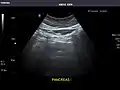

Abdominal Ultrasound (Full Exam)

STRUCTURED REPORT

(Technique: Transabdominal ultrasonography; Device: Toshiba Aplio XG)

Pancreas: Visualized portions unremarkable.

IMPRESSION:

Normal abdominal ultrasound.

Pancreas